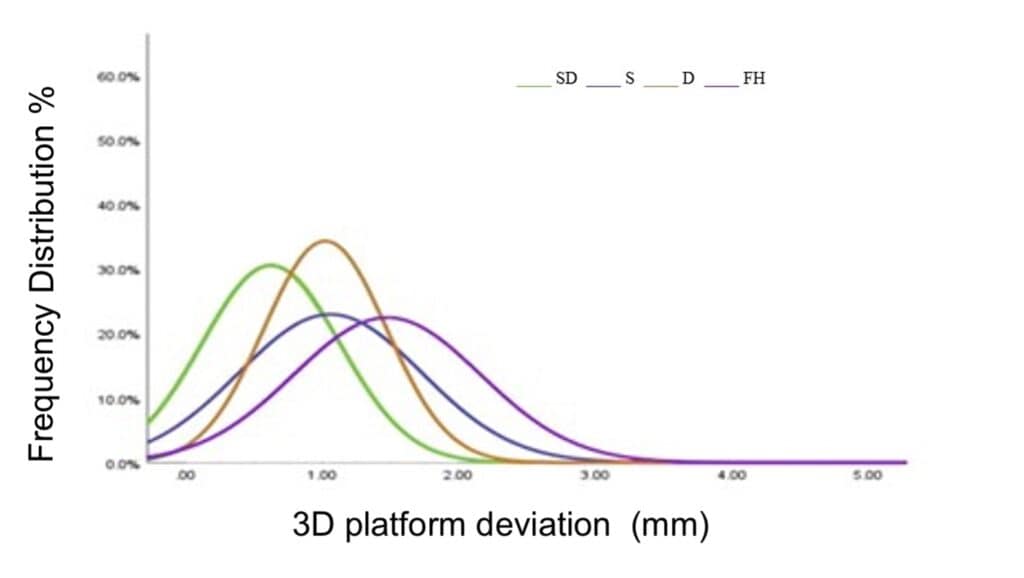

The final result: combining static and dynamic CAIS lead to the smallest deviation recorded so far a mean 3D platform deviation of 0.62 ± 0.50mm, which was some 40% less than the average 1 mm we could get with static or dynamic alone. In terms of angle, the mean was 1.24 ± 1.41, which was about half of the average 3o that static or dynamic alone would offer. Maybe the most important was actually to study the frequencies, rather than the average, and there one could see that the combined static and dynamic had achieved a significant portion of the placements with an ultra high accuracy, at least when compared to other methods. You can read more details in the recently published study by Yotpibulwong et al in Clin Oral Impl Res 2023.

Observe with the green curve the frequency distribution of the deviation at platform for the combined static and dynamic surgery. Having most of the observations left of all other curves also implies that in more than half of the cases the accuracy achieved was below the threshold of 0.8 mm. Interestingly, although static (blue) and dynamic (brown) alone have similar average, the dynamic appears less spread, possibly indicating more cases within a set of acceptable deviation.